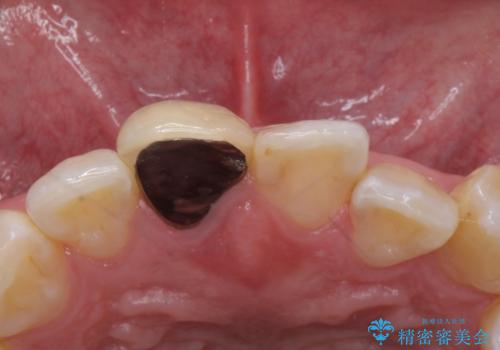

- 前歯のかぶせ物の色が気になるとのことで来院された患者様です。

セラミッククラウンで作り変えていきます。